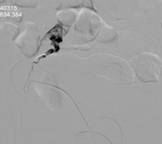

窦××,男,79岁,“右足部疼痛伴局部破溃半年”入院,间歇性跛行200米,右踝关节局部1.5×1.5cm2溃疡,第5趾底1.0×1.0 cm2溃疡,表面渗出物。糖尿病病史23年,高血压病史23年,脑梗塞病史7年。下肢动脉CTA示双下肢动脉广泛斑块形成,多发狭窄,双侧膝下动脉间断显示,大部闭塞。经药物治疗10天,疼痛消失,可自行持续行走1000米以上双下肢无不适,原足趾部溃疡愈合,踝关节部溃疡结痂。